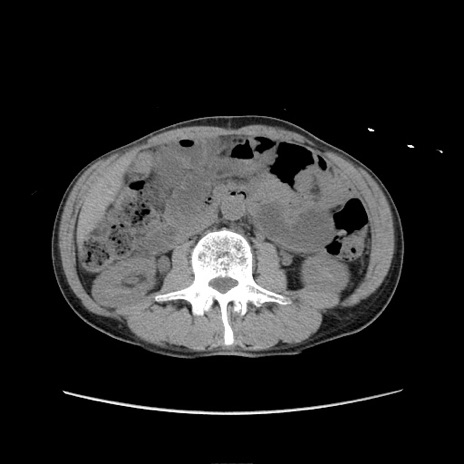

冠状断像

症例11(横断像)

【症例】 60歳代男性

【主訴】 下腹部痛

【現病歴】 本日夜中より下腹部痛の症状認め、受診。

【既往歴】 膀胱癌(膀胱全摘+尿管皮膚瘻術) 、胃癌術後

【身体所見】 BT 35.3℃、PR 58/min、BP 136/98mHg、腹部平坦、軟、腸蠕動音±、ストマ留置あり、左上腹部~正中部に圧痛あり、反跳痛なし。

【データ】WBC 5100、CRP0.01